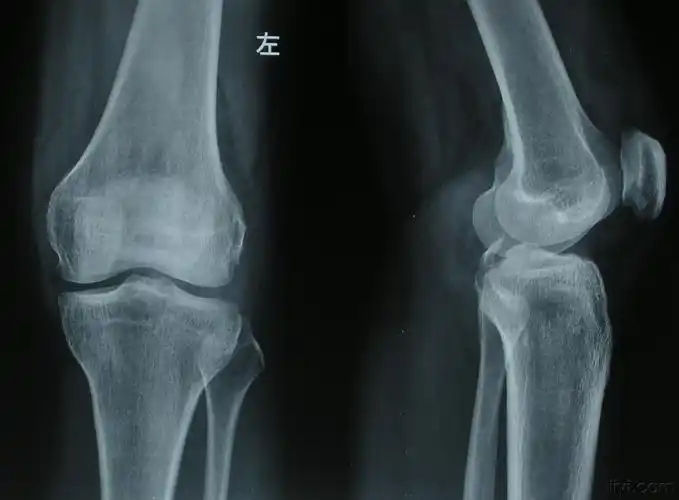

【病例讨论】左下肢严重撕脱伤 - 骨科专业讨论版 -丁香园论坛

胫骨后交叉附着点撕脱性骨折 - 骨科与显微外科专业讨论版 - 爱爱医医